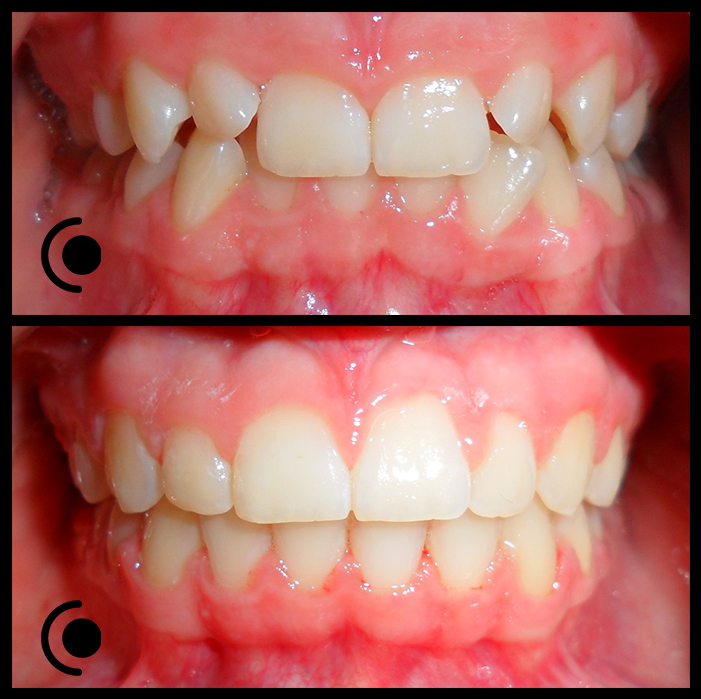

O našoj kvaliteti najbolje govore naši rezultati!